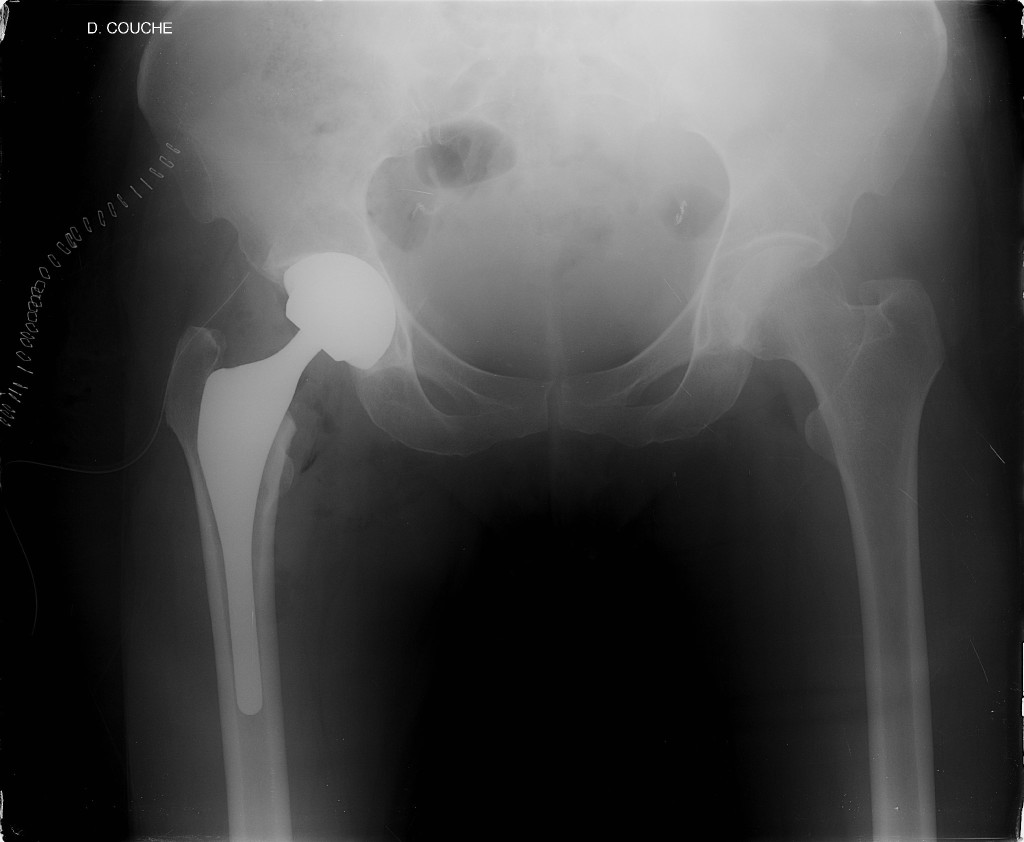

Revision Total Hip Replacement - Doctor Matthieu Meyer

prosthesis bone loosening stem acetabular femoral resorption.